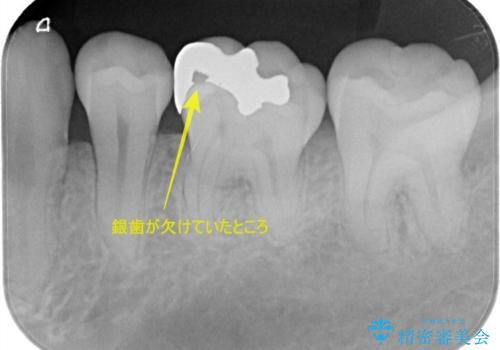

- 「銀歯を白くしたい」を主訴に来院された患者さんです。 左下6番に銀歯を被せてあり、一部分が欠けている状態でした。

銀歯と虫歯を除去しハイブリッドインレーで治療を行いました。